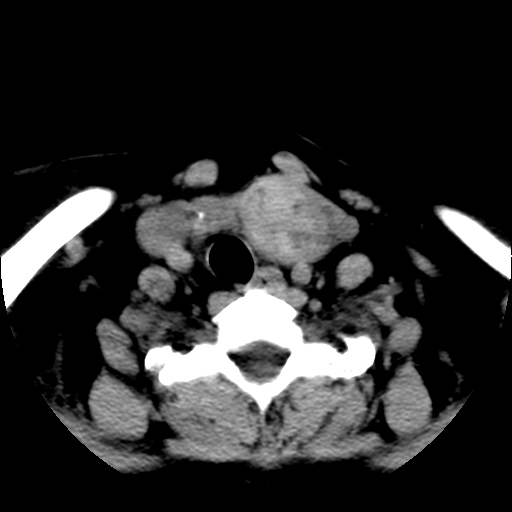

标题: CT25491:女,55岁,发现左侧甲状腺肿块一个月。 [打印本页]

标题: CT25491:女,55岁,发现左侧甲状腺肿块一个月。

女,55岁,发现左侧甲状腺肿块一个月,彩超示:甲状腺多发结节伴左叶结节液化。

考虑左侧甲状腺结节性甲状腺肿,不排除甲状腺腺瘤。